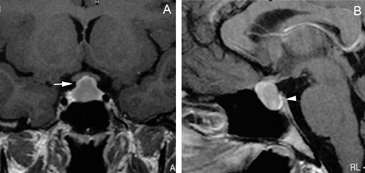

También con la mayor edad se produce involución de la glándula22, lo que puede acentuarse con el desarrollo de una hernia de la cisterna supraselar en la fosa pituitaria, que en grados avanzados constituye un aracnoidocele selar. En estos casos la silla turca puede estar aumentada de tamaño sin que exista un tumor; esto se debe a las pulsaciones del líquido cefalorraquideo(LCR) transmitidos a través de la apertura normal del diafragma selar, que en un 20% de la población puede estar ausente o presentar una dehiscencia adquirida, lo que inicialmente fue descrito en patología como "silla turca vacía"23. Esta situación de vacuidad no es tal, porque en realidad la silla turca está ocupada por líquido cefalorraquideo y una glándula pituitaria aplanada, con un tallo pituitario elongado (Figuras 9A y 9B), condición que se observa con mayor frecuencia en mujeres sobre los 50 años, obesas y multíparas. Se ha descrito en un 5,5 % de las autopsias y generalmente se trata de una condición primaria, habitualmente asintomática. En los casos secundarios, cuando hay causas como la cirugía o radioterapia, puede asociarse con alteraciones del campo visual por adherencias que deforman el quiasma óptico24.

Figura 9A y B. Cortes sagitales, secuencias T1wl con Gadolinio y T2w, muestran la hipófisis en la porción inferior de la fosa pituitaria, lo que es secundario a una herniación de la cisterna supraselar (flecha). Obsérvese que el tallo pituitario esta también descendido. La secuencia T2w permite confirmar que la señal del líquido en la fosa pituitaria es similar al LCR del IV ventrículo (punta de flecha). Tumores pituitarios